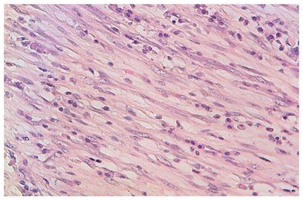

A 45year old male patient presented with a history of dyspnoea and cough since 8months. The patient was well built and nourished. His vitals were stable. Plain radiograph of chest, CT thorax was normal. Diagnostic bronchoscopic was done, the bronchial brushing was taken and was found to be positive for pulmonay tuberculosis (PTB). The patient was started on anti-tubercular therapy (ATT). He completed 6months of therapy and there was marginal reduction in the symptoms. A repeat CT thorax was done showing pleural thickening with hyperinflated left lung and bronchiectatic changes multiple patchy areas of consolidation in bilateral lungs. A CT guided biopsy was taken from the Left pleural thickening. The microscopy showed a mixed feature of spindle cells interlaced with plasma cells and lymphocytes. Immunohistochemistry (IHC) showed positivity for smooth muscle actin and vimentin and ki-67 index was 12%, the ALK was negative confirming the diagnosis of IMT. PET-CT was done which also confirmed the findings as in the CT thorax, with hyper-metabolic uptake in the left pleura and bilateral supraclavicular areas. The patient was continued on ATT till 9months, as well as started on pulsed dose steroid therapy starting dose at Oral prednisolone 30mg was started for 10days and tapered with 5mg decremental doses over a period of 4weeks (Figure 1–3).

Figure 3 Spindle cells arrayed in fascicles, mixed with inflammatory cells (medium magnification).

The biopsy is necessary to confirm the diagnosis, which usually shows a combination of inflammatory cells and mesenchymal cells which mainly is the plasma cells, histiocytes, lymphocytes and spindle cells Pettinato et al.,5 has described IFT histologically to be a an inflammatory cells with proliferative myofibroblasts and fibroblasts, with IHC positive for vimentin and smooth muscle actin.6 The IMT can invade blood vessels but a rare occurrence, as it infiltrates the lung with the inflammatory cells, it is very difficult to differentiate as the normal lung architecture gets distorted. The imaging studies done at baseline was normal, but a repeat CT thorax was done showing pleural thickening with hyper inflated left lung and bronchiectatic changes multiple patchy areas of consolidation in bilateral lungs. PET-CT confirmed the findings with hyper-metabolic uptake in the bilateral supraclavicular areas. In our case the biopsy of the pleural thickening showed mixed areas of spindle cells interlaced with plasma cells and lymphocytes. IHC positive for smooth muscle actin, vimentin and ALK negative, confirming IMT.